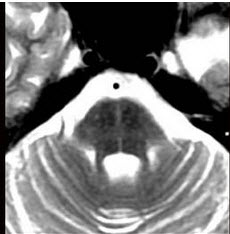

患者,男,55岁,渐起出现直立时头昏,直立性低血压2年,近半年出现眼球震颤、构音困难、步态不稳、共济失调、震颤及精神异常等症状,头颅MRI如图示,可采用的治疗方法为( )

A:平卧时适当抬高头部

B:床上坐起或下地时应快速

C:穿弹力紧身衣裤和弹力长袜

D:使用α受体拮抗剂盐酸米多君

E:使用钙离子拮抗剂尼莫地平等